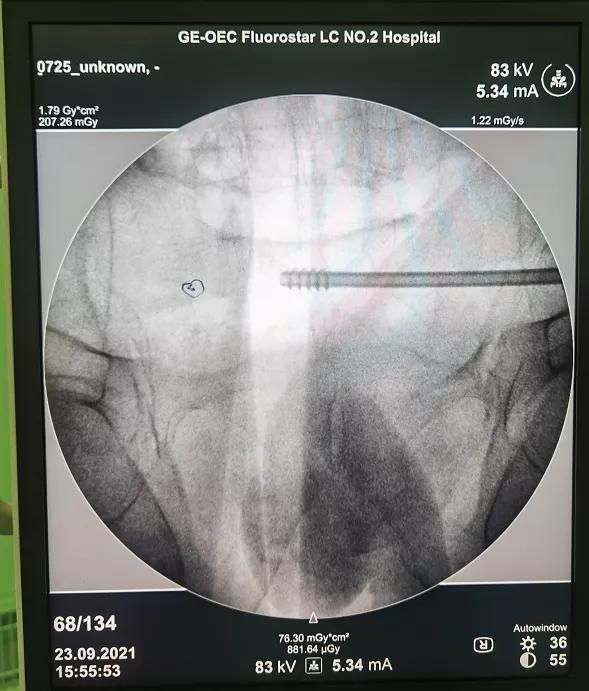

病人王**,男性,78岁,因摔伤致骨盆前后环骨折入院,患者手术意愿强烈,鉴于患者年龄较大,经科室内讨论,决定给予患者闭合复位经皮微创骶髂螺钉、耻骨支螺钉内固定术,在刘德强主任的指导下,都芳涛、方继锋、范孟坡、刘斌医师治疗团队,结合患者术前影像学资料,精确规划进钉点、进钉角度,在腰麻下进行手术治疗,术中反复进行C臂多角度透视,确定螺钉位于安全区内,顺利置入螺钉,术中出血约10毫升。目前患者在张来民护士长、路秀娥专职护师的精心护理下,恢复满意。

术中影像